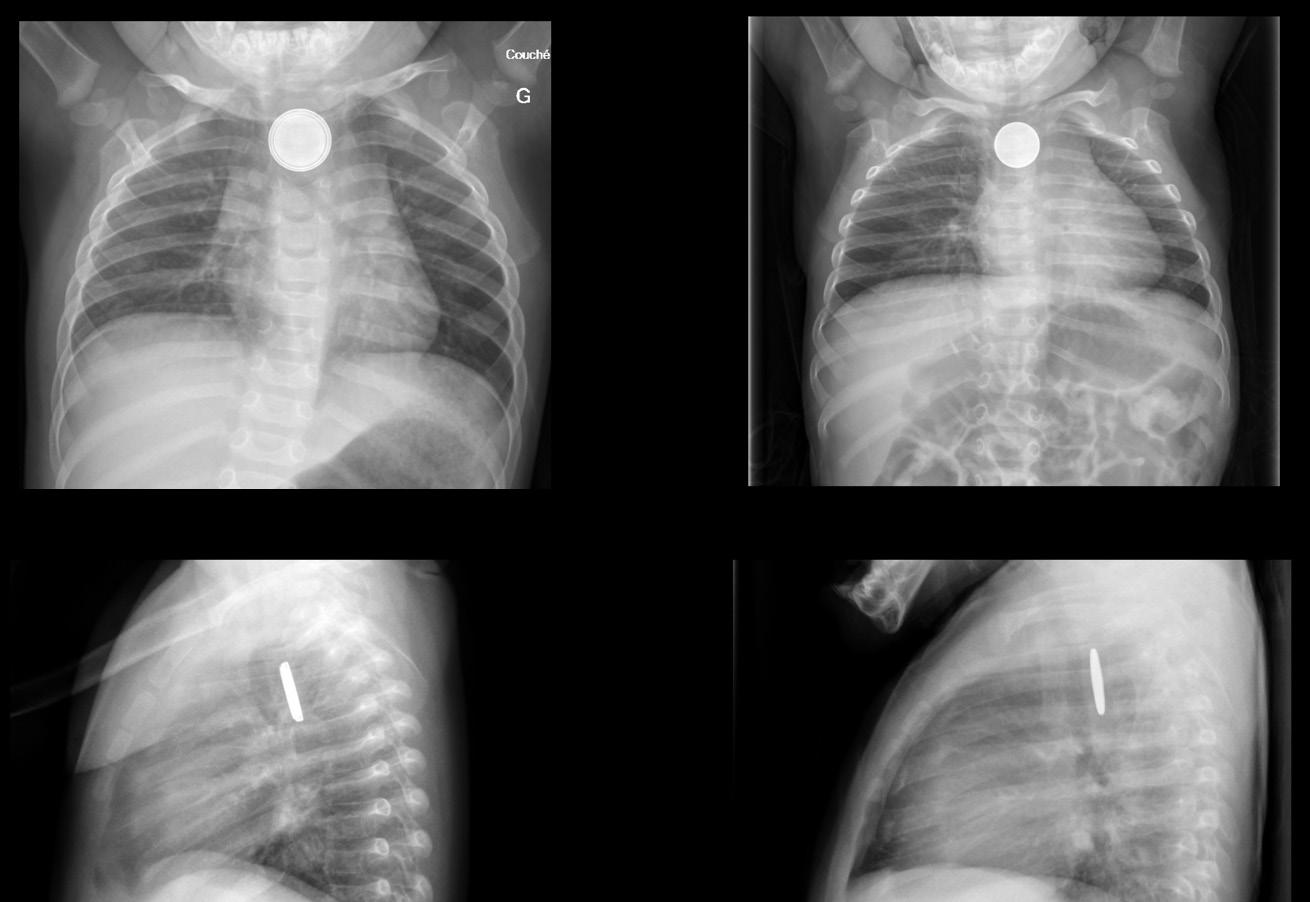

Ingestion de corps étranger par les enfants : épidémiologie, facteurs de risque et prise en charge